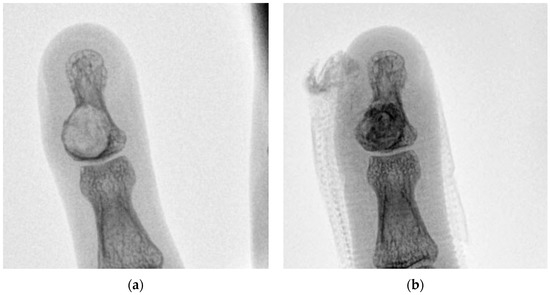

5 | 36 M | 1 | Left little finger P3 | 10 | Enchondroma | 25 |

7 | 71 M | 2 | Right middle finger P3 | 20 | Epidermoid cyst | 27 |